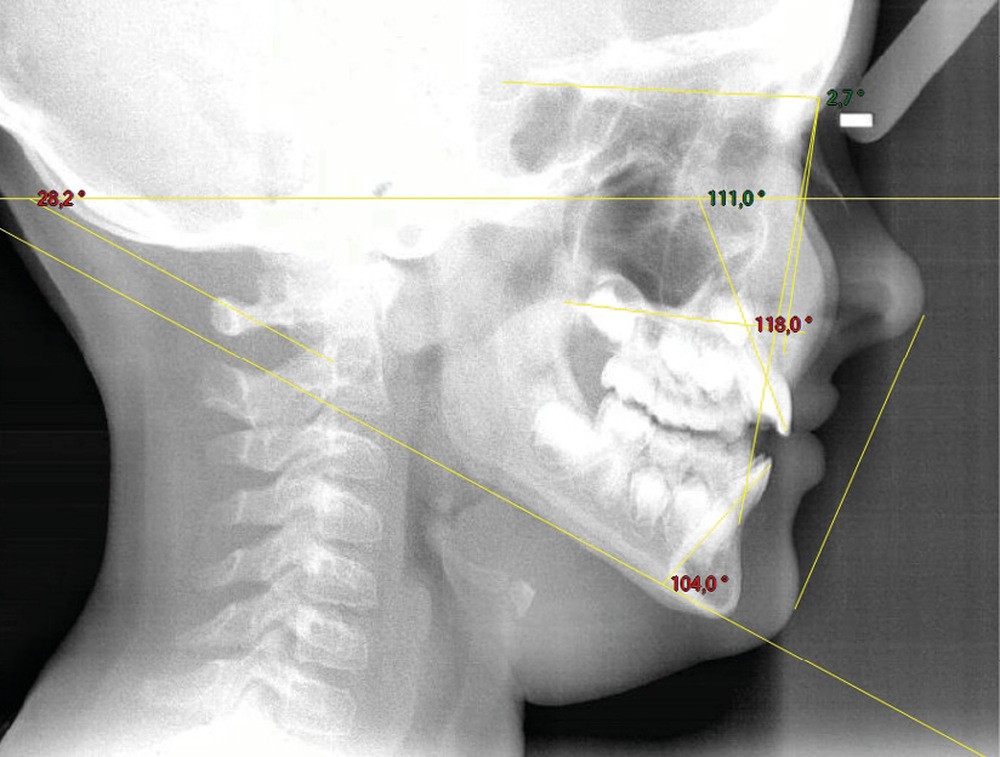

Quelques années plus tard, au moment de démarrer sa prise en charge orthodontique, la patiente présentait à nouveau une béance antérieure, un décalage des milieux incisifs de 2 mm et le problème transversal avait récidivé. Lors de l’examen clinique, elle présentait un inversé d’occlusion bilatéral postérieur et une ventilation buccale exclusive. À la suite du refus de réaliser l’amygdalectomie de façon précoce, elle ronflait toujours et sa déglutition ne s’était pas modifiée malgré des séances d’orthophonie (fig. 7 à 15).